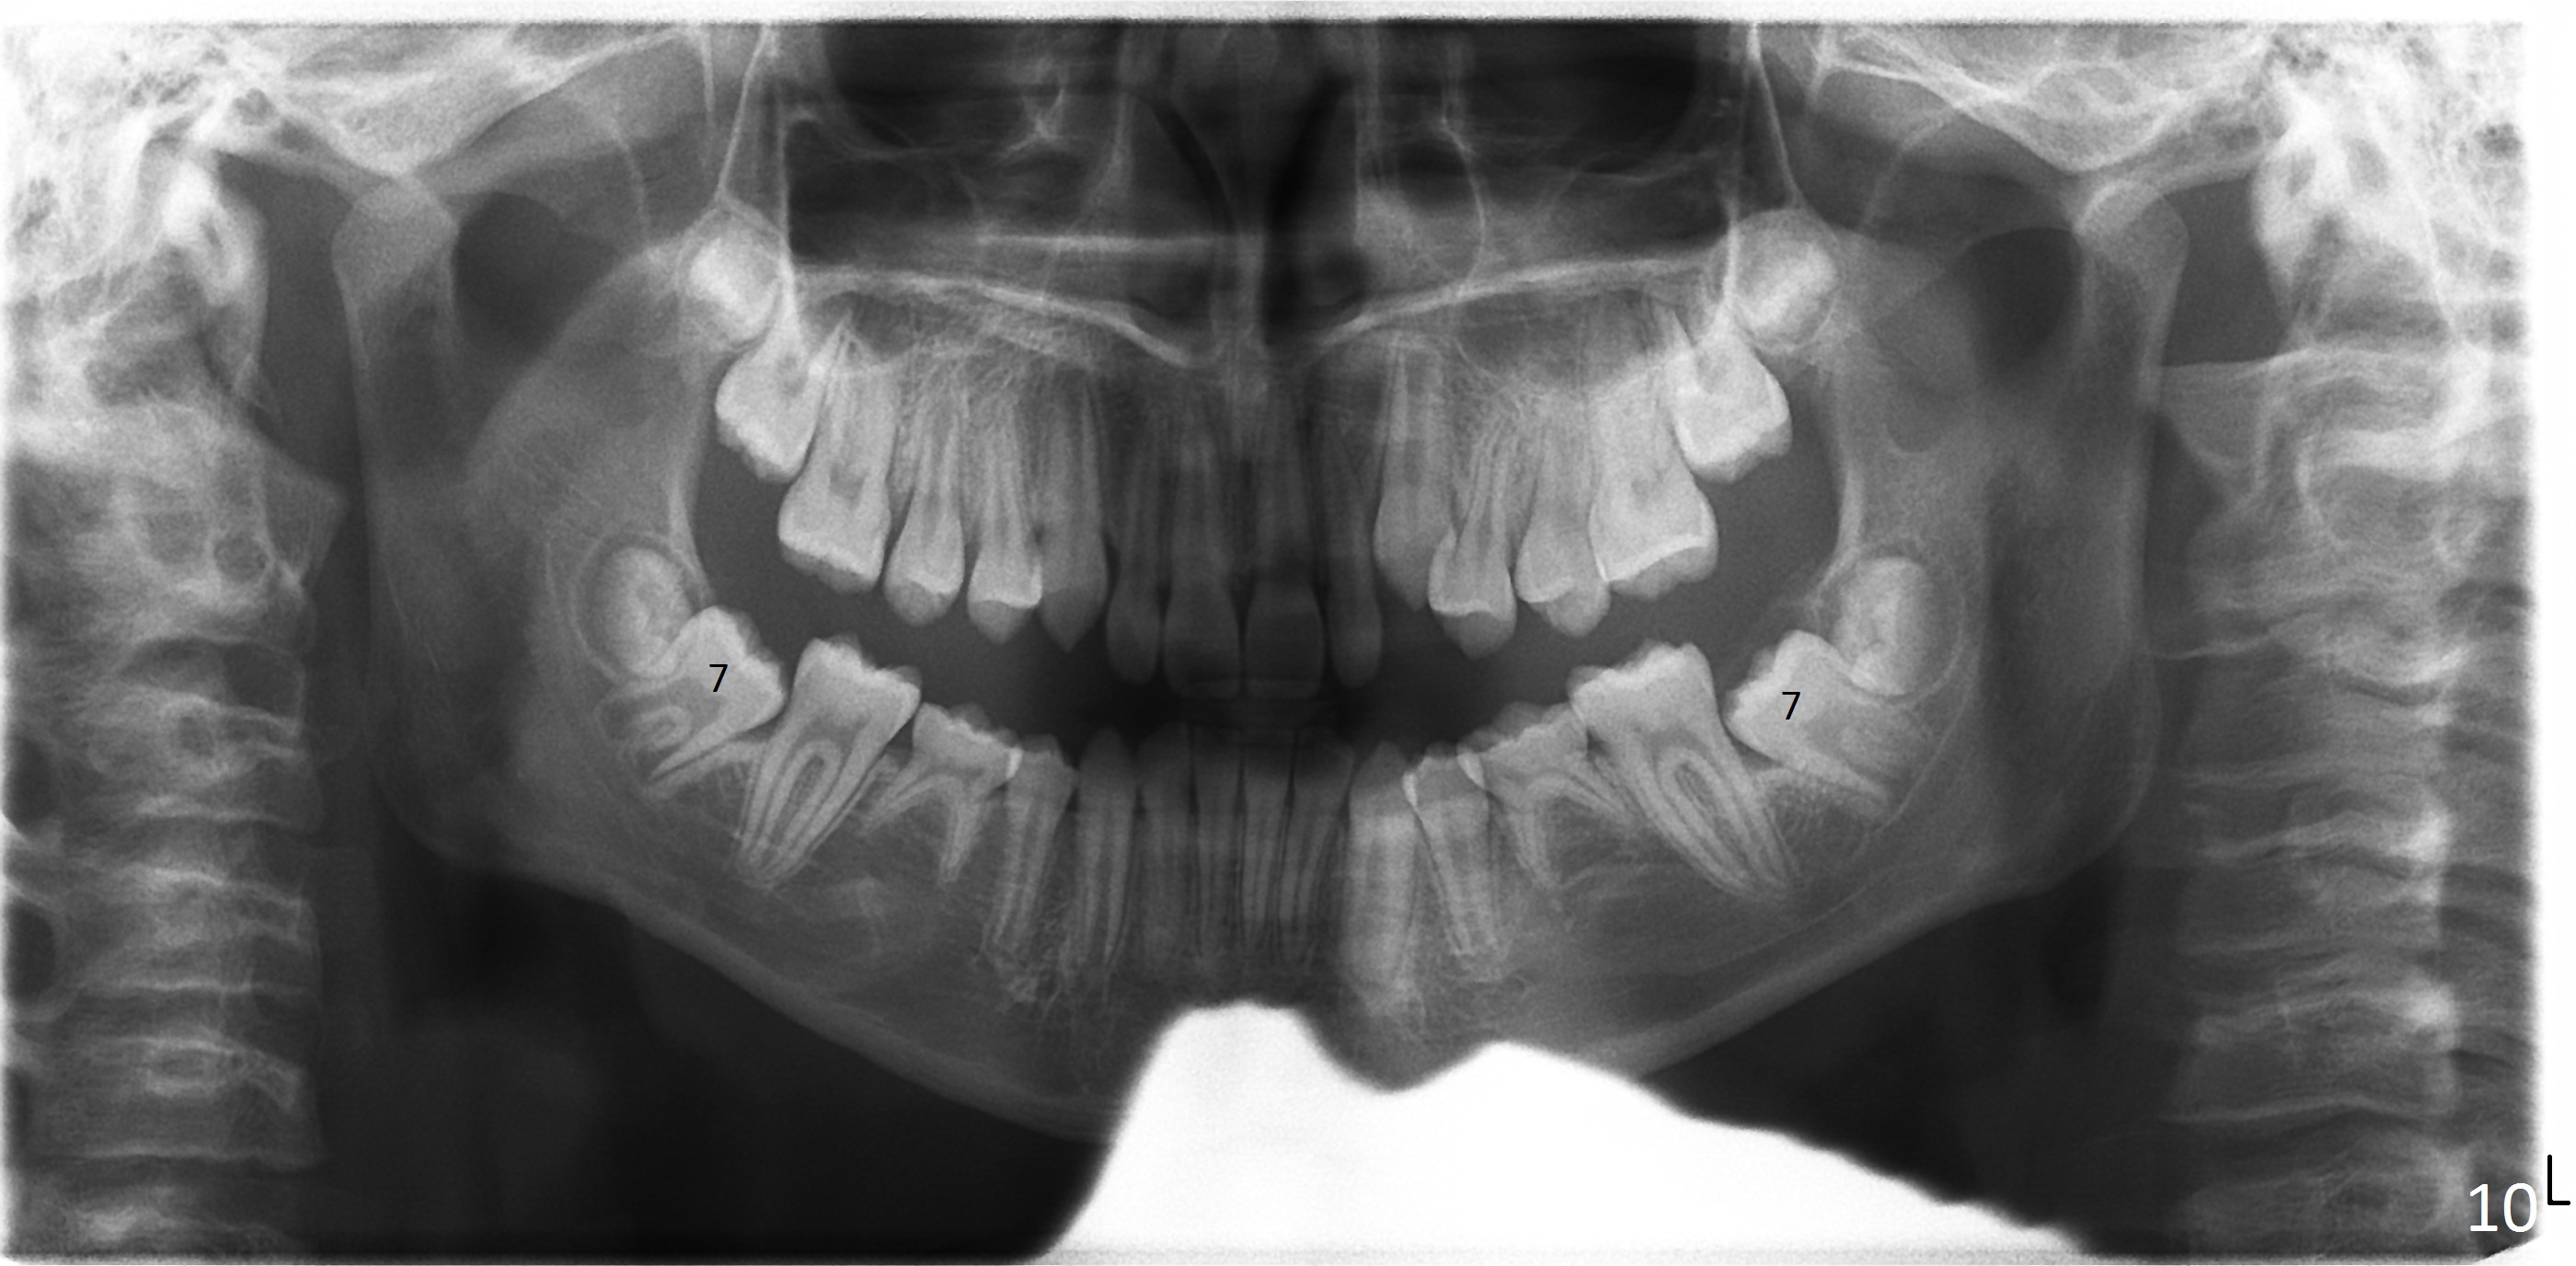

A 11-year-old boy has shorter lower 1/3 face (Fig.1,2) with light concave profile, especially the lower lip (Fig.3).  There is anterior deep bite (Fig.4) with Class II posterior occlusion (Fig.5,6).  UL2 is microdontia (Fig.7 *), while the Lower Es are retained (Fig.8).  Preop (2015_01_07) Ceph (Fig.9) and Pan (Fig.10) show ectopic L7s and congenitally missing L5s.

Brackets were placed on 2015_09_06 (Fig.11-13, Phase I pre-orthopedic tooth movement, leveling in advance of Herbst appliance therapy using ankylosed Es).   Six months later (Fig.14-16), LR7 did better, LL7 did not and will need intervention. But intrusion of L 3-3 looks good.